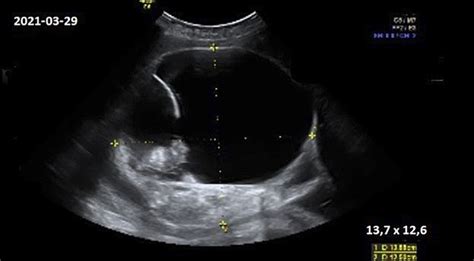

- Echoskopija: Echoskopija yra plačiai naudojama vaisiaus apsigimimų diagnostikai iki gimimo. Ji padeda anksti nustatyti patologiją, keliančią grėsmę motinai arba jos vaisiui.

- Ultragarsinė fetometrija: Šis metodas padeda įvertinti vaisiaus augimą ir galimų raidos ydų paiešką.

Nėštumo metu, ypač antrojo trimestro pradžioje, moteris gali jausti mieguistumą, vėliau atsiranda energijos stoka. Taip pat gali pasitaikyti nemalonių išskyrų iš makšties, kurias gali sukelti grybelinė infekcija. Vaisiaus dydis nėštumo viduryje yra panašus į melionio, placenta auga ir storėja, atitinkamai aprūpindama vaisių deguonimi ir maistinėmis medžiagomis. Vaisiaus proporcijos vis labiau panašėja į naujagimio, nors galvutė išlieka neproporcingai didelė. Kūnas, iš pradžių sudarytas iš kremzlių, pamažu virsta kaulais. Vaisius pradeda tyrinėti savo kūnelį ir aplinką, daro čiulpimo judesius, kurie yra gyvybinis refleksas. Vaisiaus klausos pojūtis vystosi, jis pažįsta mamos virškinimo sistemos garsus ir didžiųjų kraujagyslių šnaresį, taip pat pradeda suvokti mamos pasaulio garsus ir tėčio balsą. Akys jau jautrios šviesai, nors vokai dar užmerkti. Šiuo laikotarpiu vaisius aktyviai juda, jo padėtis vis dar nepastovi. 18-20 nėštumo savaitę atliekamas ultragarsinis tyrimas, kurio metu matuojamas vaikelio dydis, vertinama placentos vieta, vaisiaus vandenų kiekis, apžiūrima vaisiaus širdis, kaukolė ir vidaus organai.

Specialistų rekomendacija vartoti nėščiosioms skirtus vitaminus priklauso nuo ankstesnio nėštumo eigos ir mitybos subalansuotumo. Svarbu maitintis pagal sveikos mitybos principus. 11-13 nėštumo savaitę atliekamas detalus ultragarsinis tyrimas, kurio metu nustatoma preliminari gimdymo data, apžiūrimos pagrindinės vaisiaus kūno dalys, smegenų struktūra, ieškoma chromosominėms genetinėms ligoms būdingų žymenų. Vienas svarbiausių rodmenų - sprando raukšlės (vaiskumo) matmuo.